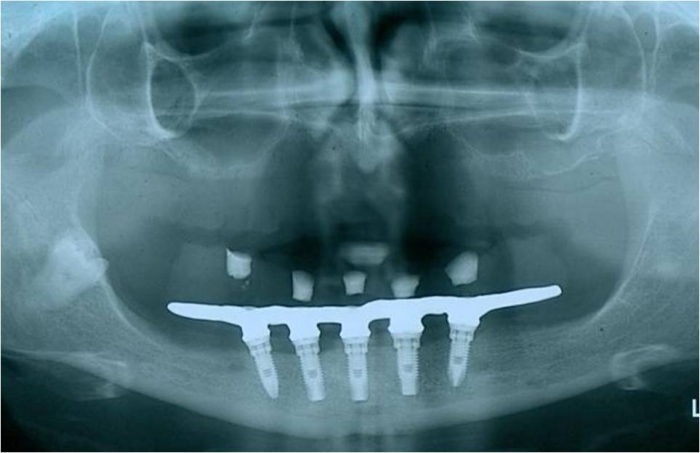

Raio x inicial